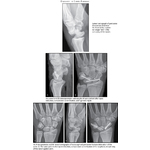

Dislocation of Carpus: Radiology